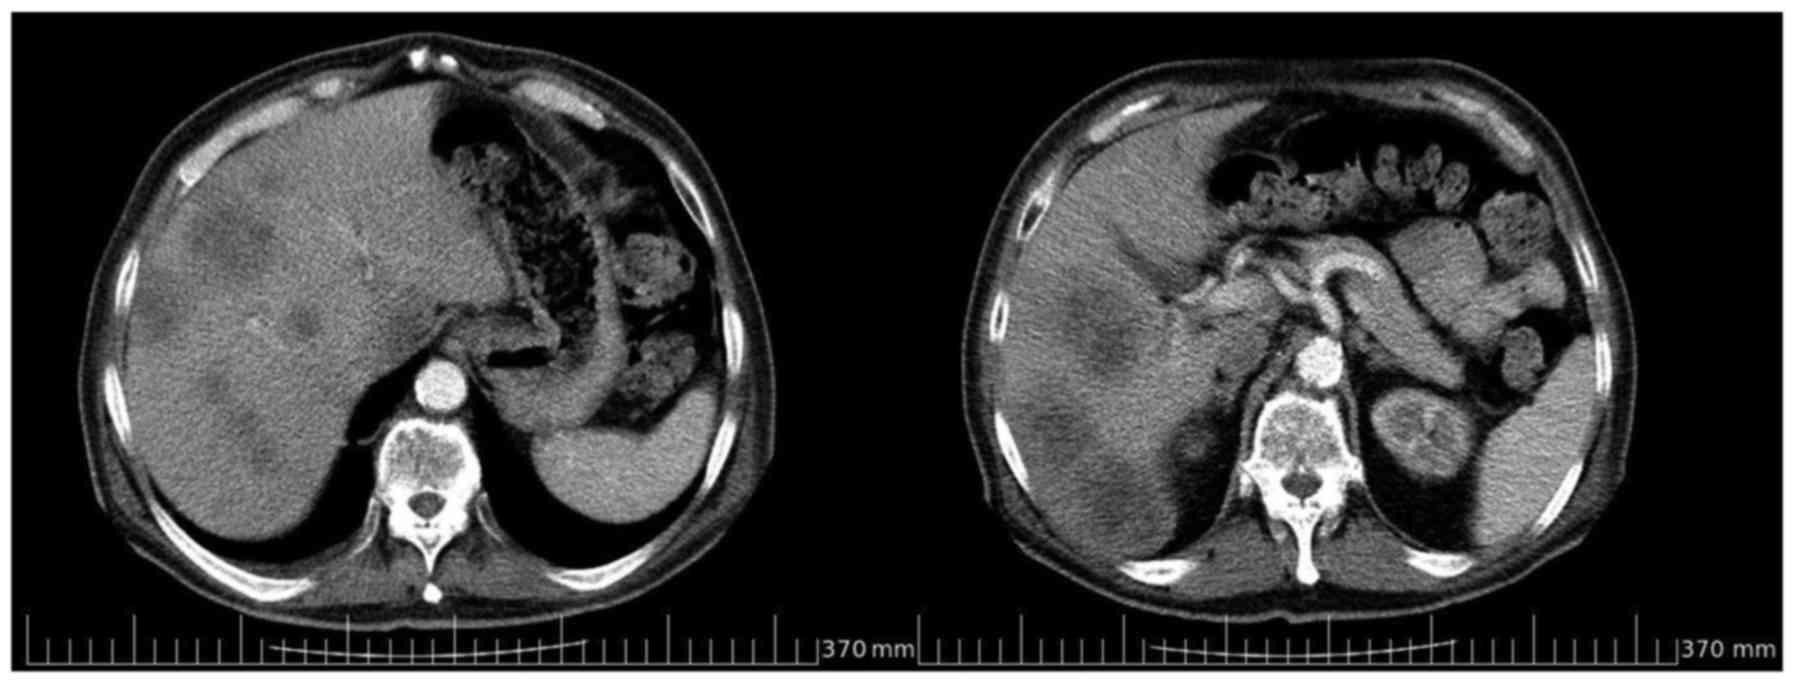

a computed tomography (CT) scan confirmed abnormal liver density,

the presence of multiple, solid nodules in the left and right

lobes, and wall thickening of the sigmoid colon (Fig. 1). These findings required further